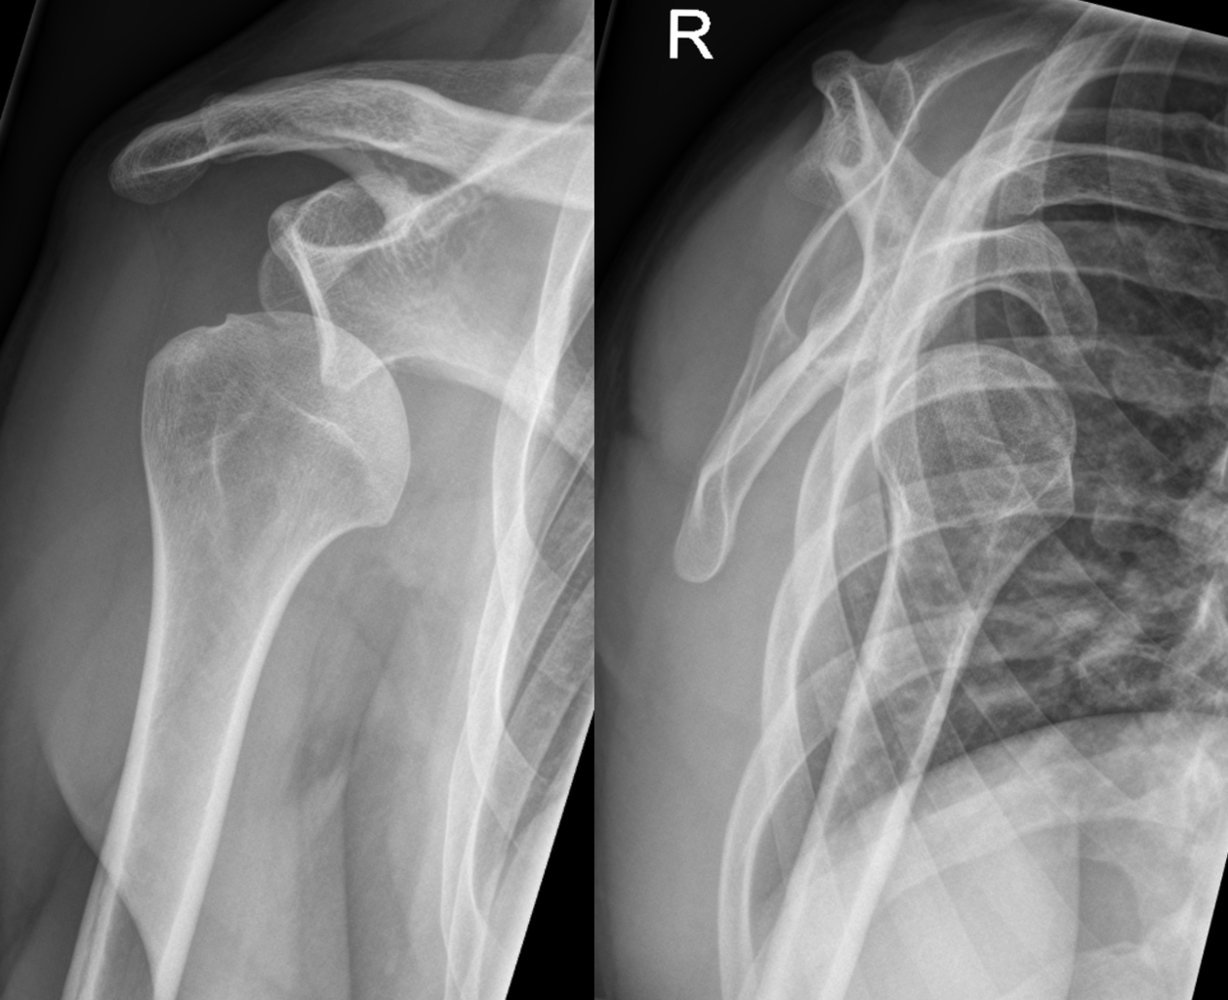

Anterior shoulder dislocation

Anterior dislocation of shoulder :

When dislocation occurs in anterior portion of the shoulder specially sub-glenoid,sub-coracoid, sub- clavicular is known as anterior shoulder dislocation.

3) Carry out an x ray to confirm the diagnosis.